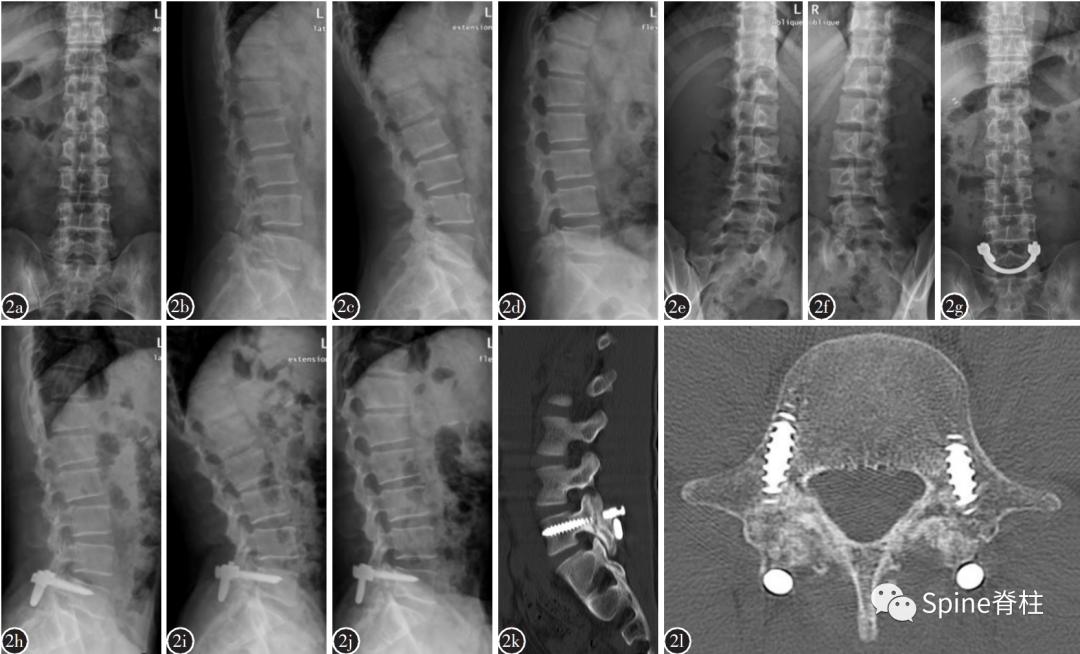

Morita教授对185例峡部裂患者(346个峡部断裂,39.6%为早期,29.5%为进展期和30.9%为终末期)研究发现,Morita分型中早期患者73.0% 经保守治疗后峡部断端出现愈合,进展期患者仅38.5%经保守治疗后愈合,而终末期患者经保守治疗后未见愈合病例。因此,对于终末期峡部裂患者,已出现假关节,保守治疗是无效的,建议早期手术治疗。

一项采用支具固定、限制活动进行保守治疗的前瞻性研究发现:

- 峡部裂早期的融合率为94%,融合时间平均为3.2月;

- 进展期伴椎弓根水肿的融合率为64%,融合时间为5.4月;

- 进展期不伴椎弓根水肿的融合率为27%,融合时间为5.7月;

- 终末期峡部裂融合率为0。

对于终末期,假关节形成,保守治疗是无效的,只能通过手术修补达到融合。